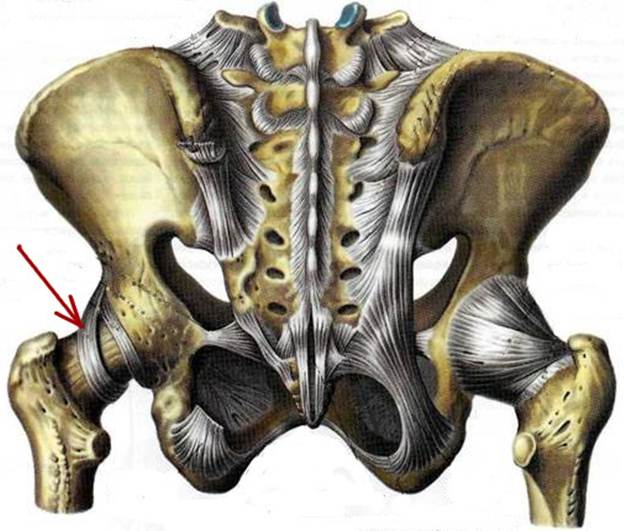

S: На рисунке обозначен art. Coxae (латинский язык).

S: Стрелка указывает на zona orbicularis

S: Стрелка указывает на lig. Ischiofemorale

S: Стрелки указывают на lig. iliofemorale

S: Стрелка указывает на lig. pubofemorale